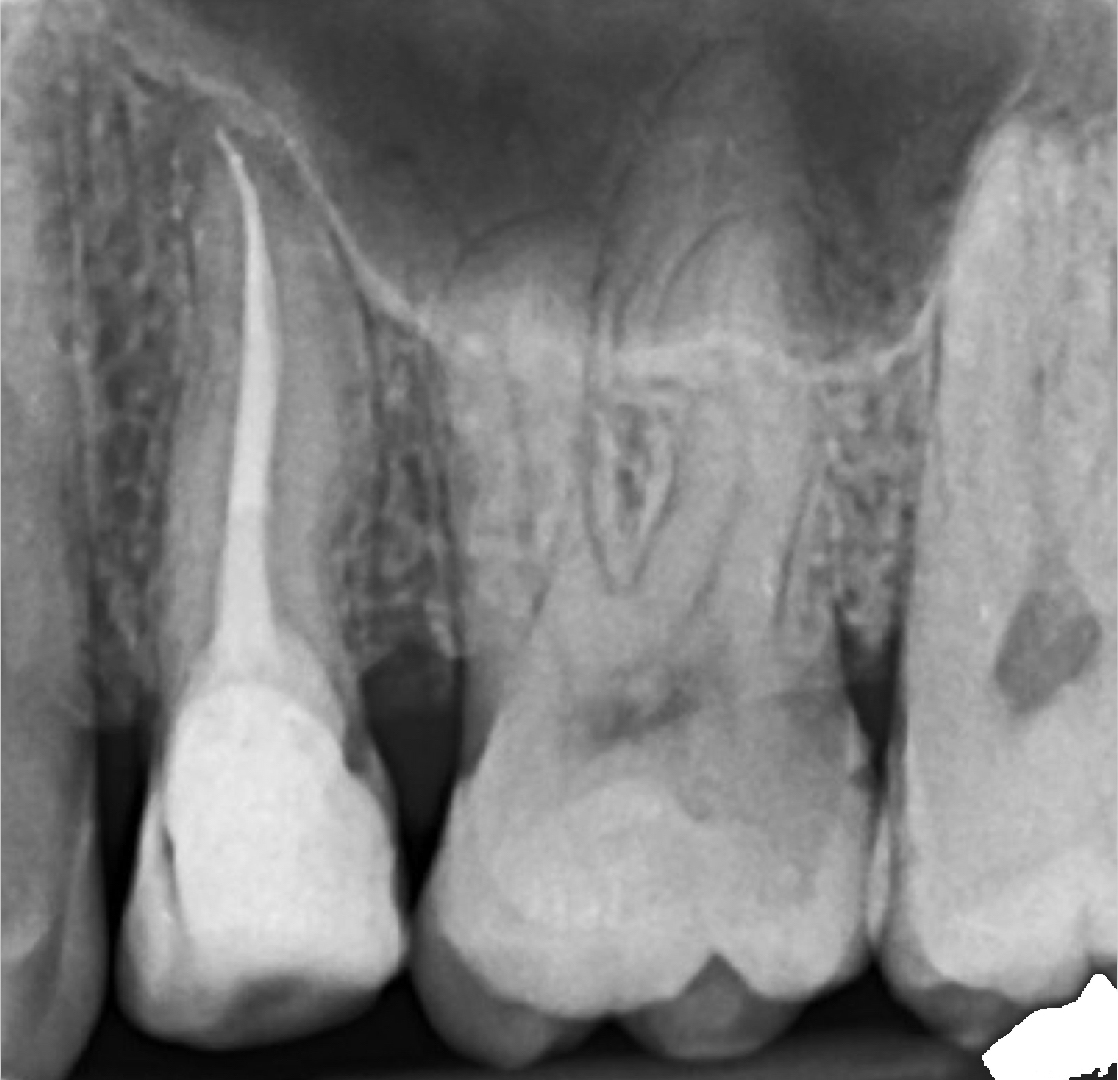

Incrustații integral-ceramice (onlay) pe dinți fără tratamente de canal și plombe

Protejarea molarului cu incrustatie onlay.